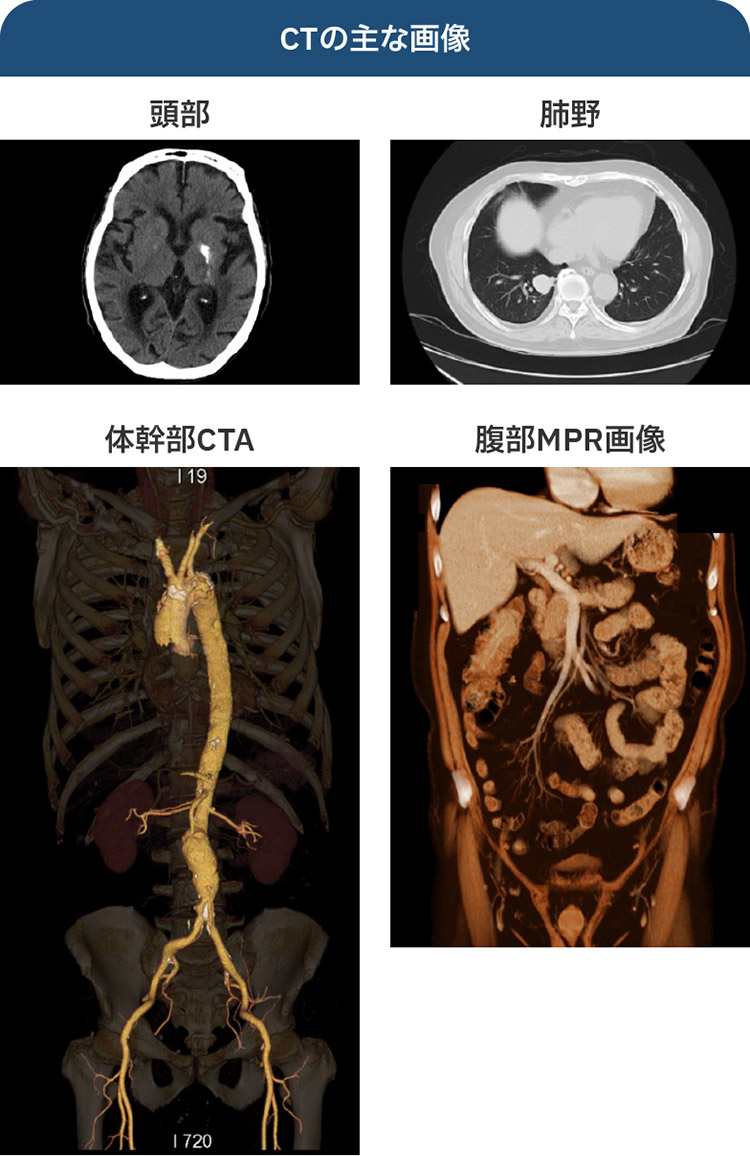

「マイヤース腹部放射線診断学 発生学的・解剖学的アプローチ」太田 光泰定価: ¥ 14000#太田光泰 #太田_光泰 #本 #自然/医療・薬学・健康